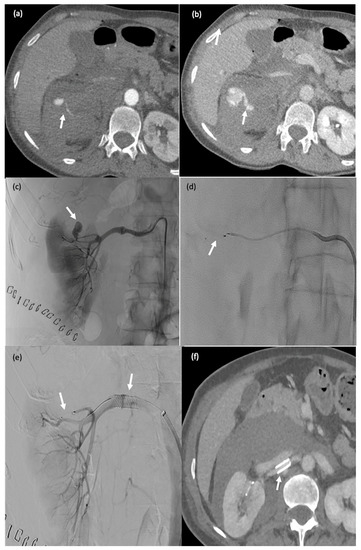

Figure 5. This 65-year-old female patient (#10) started experiencing severe lumbar pain six days after partial nephrectomy for renal cancer with renal artery clamping. Her haemoglobin level dropped by 3 g/dL and her haemodynamics were unstable. Active postoperative bleeding was suspected, and she was taken to the computed tomography suite. (a,b) Active retroperitoneal bleeding (false aneurysm) (arrow). (ce) Angiography showing a false aneurysm of the superior polar artery of the right kidney ((c), arrow), which was embolised using an MPV-3Q ((d), arrow); stenting of the renal artery (clamp injury) ((e) arrow). (f) CT two days after embolisation: there was no active bleeding and the MVP-3Q and stent were properly positioned (arrow).